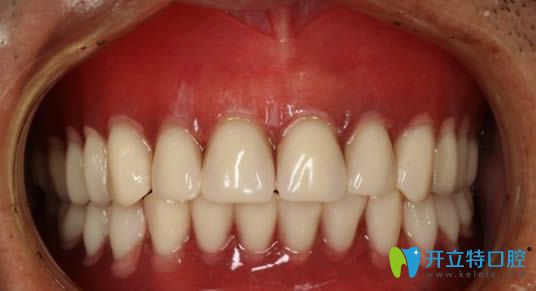

在杭州美奧口腔做完全口即刻種植牙后的照片

在這里提醒大家,若條件允許,請(qǐng)優(yōu)先考慮種植牙而非活動(dòng)假牙。我個(gè)人體驗(yàn)到種植牙的咀嚼功能幾乎與真牙無異,它對(duì)日常飲食的影響極大。因此,希望大家不要因?yàn)閮r(jià)格因素而將就,畢竟種植牙的高性價(jià)比是不容忽視的。